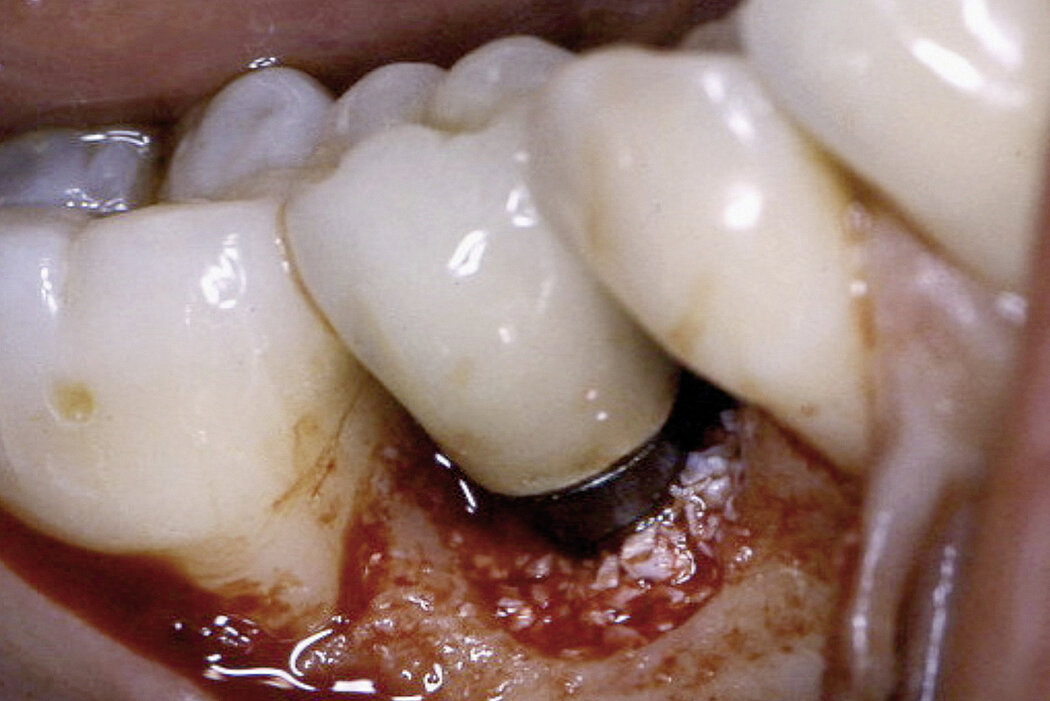

种植体周围炎

- 火山口状骨量缺损

- 探诊时出血或出脓

- 种植体不摇动

- 种植体周围的探针深度大于4mm

当以上列出的所有病症同时出现,即可诊断为种植体周围炎。如果只有一个病症出现,则不能充分诊断为种植体周围炎

临床案例:通过组织再生的手术治疗方法治愈种植体周围骨缺损,并获得令人满意的远期治疗效果。

临床病例